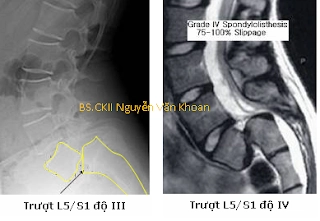

Trượt đốt sống do khuyết eo đốt sống mức độ nặng và trượt đốt sống do loạn sản đốt sống là một dạng khác với trượt đốt sống mức độ nhẹ do khuyết eo đốt sống. Gọi là trượt nặng khi di lệch hơn 50% bề mặt thân đốt sống. Trượt nặng thường kèm theo gù vùng thắt lưng-cùng. Trượt nặng hiếm gặp hơn trượt nhẹ, trong các trường hợp trượt đốt sống do khuyết eo đốt sống thì trượt nặng chỉ chiếm dưới 10% và thường gặp ở lứa tuổi thanh thiếu niên.

Độ 3: trượt 51-75% thân đốt sống.

Độ 4: trượt 76-100% thân đốt sống.

Độ 5: trượt hoàn toàn, đốt trên hoàn toàn rơi khỏi bề mặt thân đốt dưới.